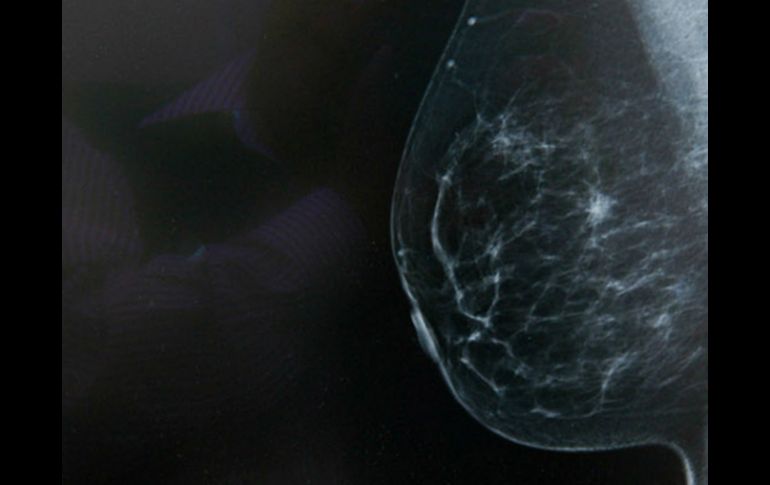

Tecnología | El compuesto conocido como JQ1 altera la reacción de las células cancerígenas Descubren fármaco que reduce la expansión del cáncer de mama El compuesto conocido como JQ1 altera la reacción de las células cancerígenas ante la hipoxia o falta de oxígeno Por: EFE 13 de junio de 2016 - 10:15 hs Cuando este tipo de tumor se acostumbra a los niveles bajos de oxígeno, su biología se altera y se vuele resistente a terapias comunes. NTX / ARCHIVO LONDRES, INGLATERRA (13/JUN/2016).- Un grupo de investigadores de Cancer Research UK descubrió un fármaco que puede reducir la expansión del tipo más agresivo de cáncer de mama, según publicó la revista Oncogene. El compuesto conocido como JQ1 altera la reacción de las células cancerígenas ante la hipoxia o falta de oxígeno, un proceso que se encuentra presente en más del 50 % de los tumores y es más común en los cánceres de mama del tipo triple negativo, el más difícil de tratar. Científicos de las universidades de Oxford y Nottingham (en el centro de Inglaterra) concluyeron en su estudio que el JQ1 provoca que el tejido cancerígeno deje de adaptarse a la carencia de oxígeno, lo que ralentiza su desarrollo. El coautor de la investigación, Alan McIntyre, afirmó que "el tratamiento de la hipoxia a veces compromete el tratamiento del cáncer de mama y el JQ1 puede ser la clave para ayudar a las pacientes de esta enfermedad". Cuando este tipo de tumor se acostumbra a los niveles bajos de oxígeno, su biología se altera y se vuele resistente a terapias comunes, razón por la que este nuevo medicamento podría cambiar la forma de combatir este cáncer, según los investigadores. Desde Cancer Research UK, Nell Barrie, apuntó que "el estudio muestra cómo funciona este fármaco" y que "podría ser una forma de detener la expansión del cáncer", aunque remarca que ahora se debe examinar "la efectividad del JQ1 sobre los pacientes". Temas Descubrimientos ciencia Ciencia médica Cáncer de mama Enfermedades Calor de hogar Lee También Cómo podrían los antibióticos incrementar el riesgo de cáncer colorrectal Conmociones cerebrales, la cuarta lesión más frecuente en partidos de la Conmebol Estas son las vacunas recomendadas en época de frío Así ha bajado la afiliación de trabajadoras del hogar en el IMSS Recibe las últimas noticias en tu e-mail Todo lo que necesitas saber para comenzar tu día Registrarse implica aceptar los Términos y Condiciones